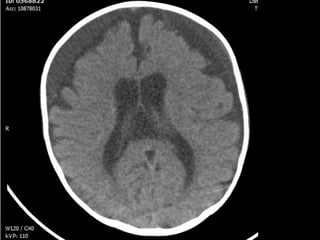

Evolución clínica A los siete meses: TAC craneal: Hematomas subdurales bilaterales. Efecto masa Trépanos bilaterales con evacuación  Colocación de drenajes bilaterales 10 meses: Asintomático. Desarrollo psicomotor normal

Evolución clínica Alos siete meses: TAC craneal: Hematomas subdurales bilaterales. Efecto masa Trépanos bilaterales con evacuación Colocación de drenajes bilaterales 10 meses: Asintomático. Desarrollo psicomotor normal

• #8 Fosa craneal media: hematoma subdural agudo TEMPORAL bilateraL. Fosa posterior: aumento de los espacios que contienen LCR. No hay sangre en fosa posterior

• #9 Hematoma frontal bilateral, mayor izquierdo.

• #10 Aumento del LCR : cisura interhemisférica. Hematoma frontal bilateral AGUDO-SUBAGUDO

• #11 Ventriculomegalia aumento de tamaño de ventrículos laterales. Hematoma subagudo bilateral frontal (menos denso que el parietal pero de mayor densidad que el LCR)

• #12 Hematoma parietal bilateral agudo (sangre hiperdensa). Aumento del espacio interhemisférica